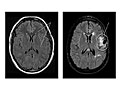

Pruebas de imágenes (MRI y CT)

Las imágenes por resonancia magnética (MRI, por sus siglas en inglés) y la tomografía computarizada (CT, por sus siglas en inglés) son pruebas por imágenes que le permiten al médico observar el cerebro y evaluar la causa y la ubicación de una posible fuente de epilepsia dentro del cerebro. Estas exploraciones pueden mostrar tejido cicatricial, tumores o problemas estructurales dentro del cerebro que pueden ser la causa de las crisis o de la epilepsia. La MRI es la prueba más útil en la mayoría de los casos. Es posible que no se hagan pruebas por imágenes después de la primera crisis, pero se recomiendan en muchas situaciones (como, por ejemplo, después de la primera crisis en adultos o después de una lesión en la cabeza).